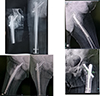

Among the short GP, a patient presented with implant failure at a 2-month interval with avascular necrosis of the femoral head. There was significant varus collapse (>5°) with a z effect. Patient underwent implant removal and arthroplasty Figure 4.

![]() |

Figure 4 (A) (AO 31–A2.3) fracture pattern, (B) AP and lateral views 2 m later post-surgery showing AVN and varus collapse, and (C) CT 3D showing z effect. |